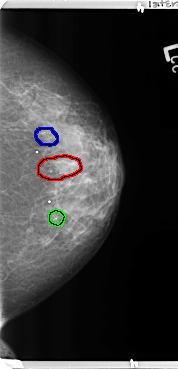

B_3364_1.LEFT_MLO

FILE: B_3364_1.LEFT_CC.OVERLAY

TOTAL_ABNORMALITIES 3

ABNORMALITY 1

LESION_TYPE CALCIFICATION TYPE PLEOMORPHIC DISTRIBUTION CLUSTERED-SEGMENTAL

ASSESSMENT 4

SUBTLETY 4

PATHOLOGY BENIGN

TOTAL_OUTLINES 1

BOUNDARY

ABNORMALITY 2

ABNORMALITY 3